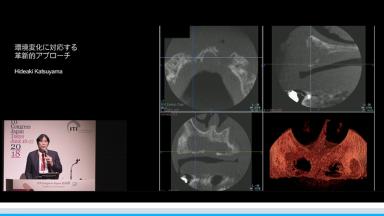

環境変化に対応する革新的アプローチ

インプラント治療において、急速な高齢化や低侵襲治療など患者のニーズの変化、審美へ要求、難症例の増加、デジタルの発展や歯科業界の全体の構造的な変化など激烈な変化が見られる。演者は革新的ななアプローチでどの様に対応するかについて解説する。